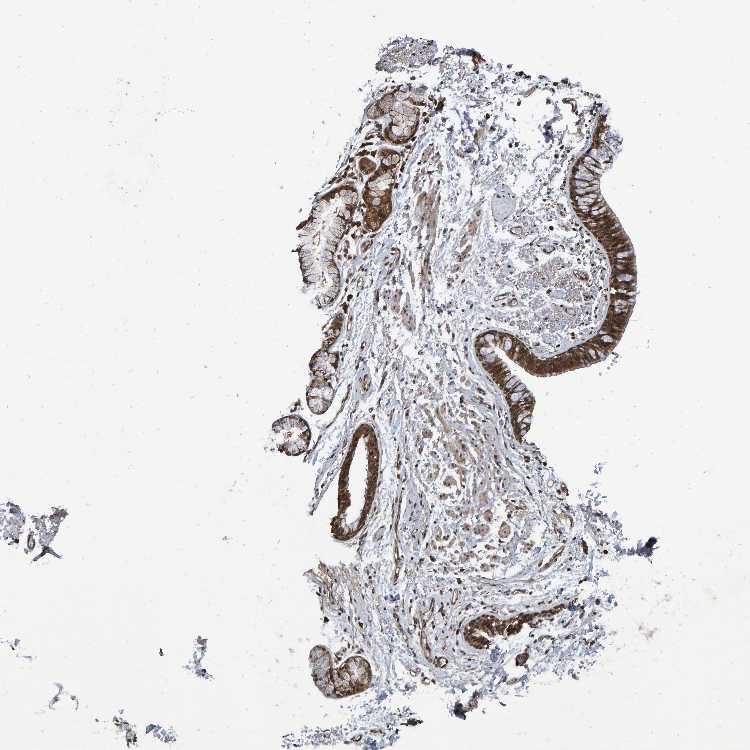

SOFT TISSUE 1 - Antibody stainingi

Antibody staining in the annotated cell types in the current human tissue is reported as not detected, low, medium, or high, based on conventional immunohistochemistry profiling in selected tissues. This score is based on the combination of the staining intensity and fraction of stained cells.

Each image is clickable and will lead to virtual microscopy that enables deeper exploration of all samples and also displays staining intensity scores, fraction scores and subcellular localization as well as patient and tissue information for each sample.

Antibody HPA000271Antibody CAB022159

Fibroblasts LowHigh

SOFT TISSUE 2 - Antibody stainingi

Fibroblasts MediumHigh